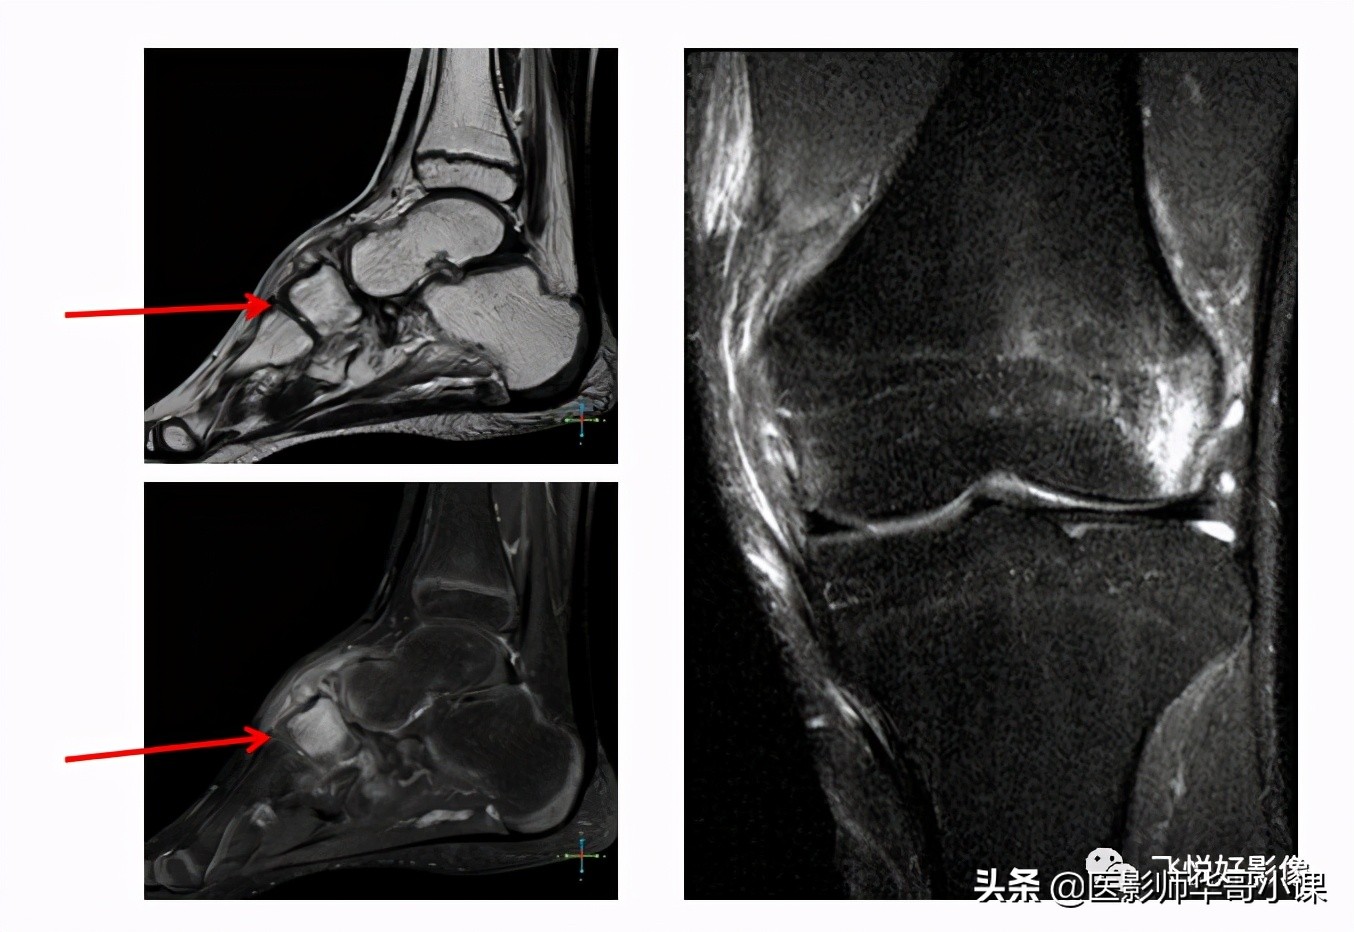

这一点在骨关节系统的诊断中尤其重要。我们知道,骨髓腔的病变在T2加权像上一般呈现高信号,而骨髓由于富含黄骨髓(脂肪组织)也呈高信号,两者缺乏对比,容易掩盖病变。左边这组图,常规T2加权像上,很难发现病变,通过压脂,可以清晰显示舟状骨骨髓水肿。